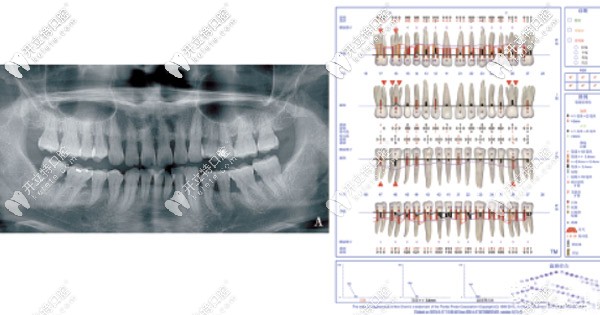

2.jpg▲曲面平展片以及剛檢查的Florida檢查表

顧客存在深覆合、深覆蓋、上下中線不齊、下前牙列擁擠等錯(cuò)頜畸形問(wèn)題,造成惡劣不利于菌斑控制的環(huán)境。

檢查時(shí)發(fā)現(xiàn)顧客的口腔衛(wèi)生情況較差,牙齦顏色鮮紅,齦緣腫脹后,以上下前牙為重。齦上牙石Ⅱ度,軟垢Ⅱ度,下頜中偏左3mm,下前牙牙列擁擠。

根據(jù)制定的新分類(lèi)來(lái)看,屬于牙周炎第Ⅲ階段,B級(jí)。根據(jù)評(píng)估系統(tǒng),評(píng)估為高風(fēng)險(xiǎn)。